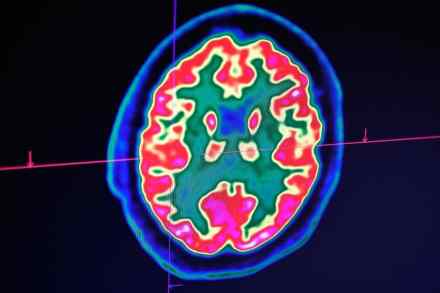

Cracking consciousness: how do our minds really work?

With scientists mapping our neurons in ever greater detail, and companies like Google claiming they're close to creating human-level artificial intelligence, the gap between brain and machine seems to be shrinking — throwing the question of consciousness, one of the great philosophical mysteries, back into the heart of scientific debate. Will the human mind — that ineffable tangle of private, first-person experiences — soon be shown to have a purely physical explanation? The neuroscientist Steven Novella certainly thinks so: 'The evidence for the brain as the sole cause of the mind is, in my opinion, overwhelming.'  Elon Musk agrees: 'Consciousness is a physical phenomenon, in my view'.